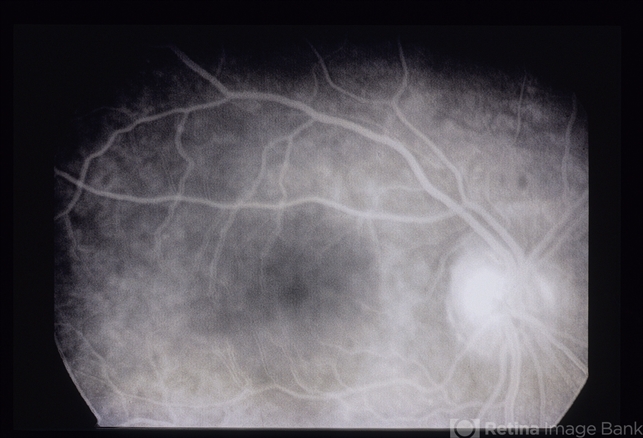

- A 23 year old white female who presented with floaters and blurred vision in the left eye for 2 weeks.